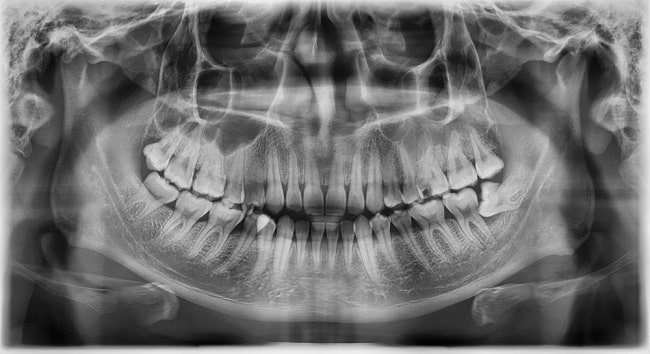

Konsensus umum untuk tata laksana kasus impaksi molar ketiga yang disertai kondisi patologis adalah ekstraksi atau pencabutan, namun tata laksana terbaik bagi kasus asimptomatik masih menjadi perdebatan. Gigi molar ketiga atau dikenal juga sebagai gigi bungsu (wisdom tooth) umumnya erupsi ketika seseorang berumur 17-26 tahun. Akan tetapi, tidak jarang gigi ini mengalami impaksi akibat kurangnya ruang erupsi di dalam rahang atau jalur erupsinya terganggu karena gigi-gigi di sekitarnya.

Prevalensi impaksi gigi molar ketiga mencapai 24%, lebih tinggi dibandingkan gigi-gigi lainnya. Walaupun impaksi gigi bukanlah suatu kondisi patologis, tetapi impaksi keseluruhan ataupun parsial berkaitan dengan kondisi-kondisi patologis seperti perikoronitis, resorpsi akar, penyakit periodontal, karies, juga kista dan tumor.[1,2]

Ekstraksi gigi molar ketiga merupakan salah satu prosedur yang paling banyak dilakukan oleh seorang dokter gigi. Di Amerika Serikat, 95% pencabutan gigi pada rentang usia 16 hingga 21 tahun adalah pencabutan gigi molar ketiga ini. [3] Pencabutan tersebut dilakukan terutama jika terdapat tanda-tanda awal atau gejala yang mengarah ke kondisi patologis.[4]